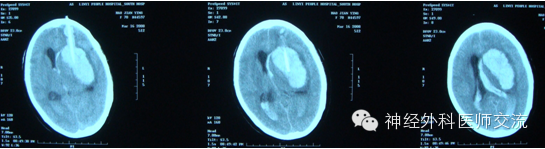

很普通的病例,术后4小时,突发脑疝,静推1瓶甘露醇,急查CT

从三通侧臂,抽不出血来。拔除引流导管,按照新的CT,从原骨孔重新置管,从新操作

远端的血清掉后,回撤导管,再液化引流

原因:术后病人烦躁、血压恶性升高,致再出血,导成血肿扩大。